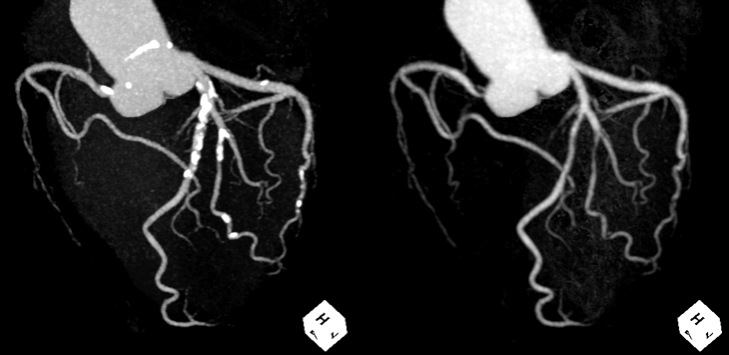

4DCT angiography

320列CTの特徴を活かし、動画による“心臓の動き”や“血流の流れ”を詳細に評価できる撮影も行なっております。

大動脈4D Flow:造影剤を使用せずに血流を動画で評価可能です。